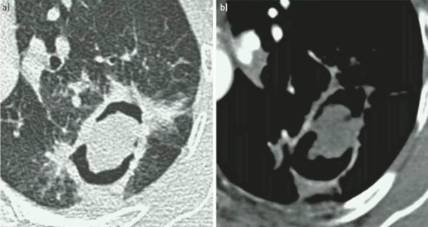

单纯肺曲菌球:非免疫受损病人,有较少或没有症状,含真菌球单发空洞,具有曲霉菌血清学和微生物学依据(阳性结果),至少观察3个月没有放射影像学的进展。

慢性空洞性肺曲霉病(CCPA):最常见,单发或多发的肺空洞(薄壁或厚壁),空洞内可包含一个或多个曲菌球或不规则的腔内物质,具有曲霉菌血清学和微生物学依据,并有明显肺部和全身症状,至少3个多月的观察有放射影像学进展(新发空洞,空洞外周浸润增加及纤维增生增加)。

曲霉结节:不常见,单发或多个结节(<3cm),有或没有空洞,常出现坏死,但不表现为组织侵袭。易与结核、肺癌、肺球孢子菌及其他疾病混淆,只能依靠组织学明确诊断。